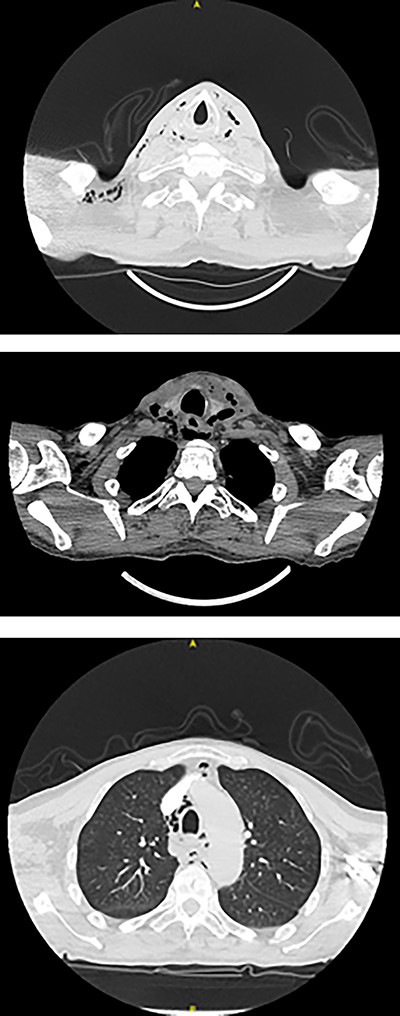

Intravenous Meropenem, Metronidazole and Fluconazole were continued, and he remained nil by mouth with nasogastric tube feeding. Water-soluble contrast swallow was undertaken after repeat CT showed emphysema progression (Fig. 3). A left sided oropharyngeal perforation was suggested.

Axial planes CT neck and thorax showing left parapharyngeal abscess with tracking into the prevertebral space, significant progression of air pockets in mediastinal and cervical soft tissue extending to right axillary region.